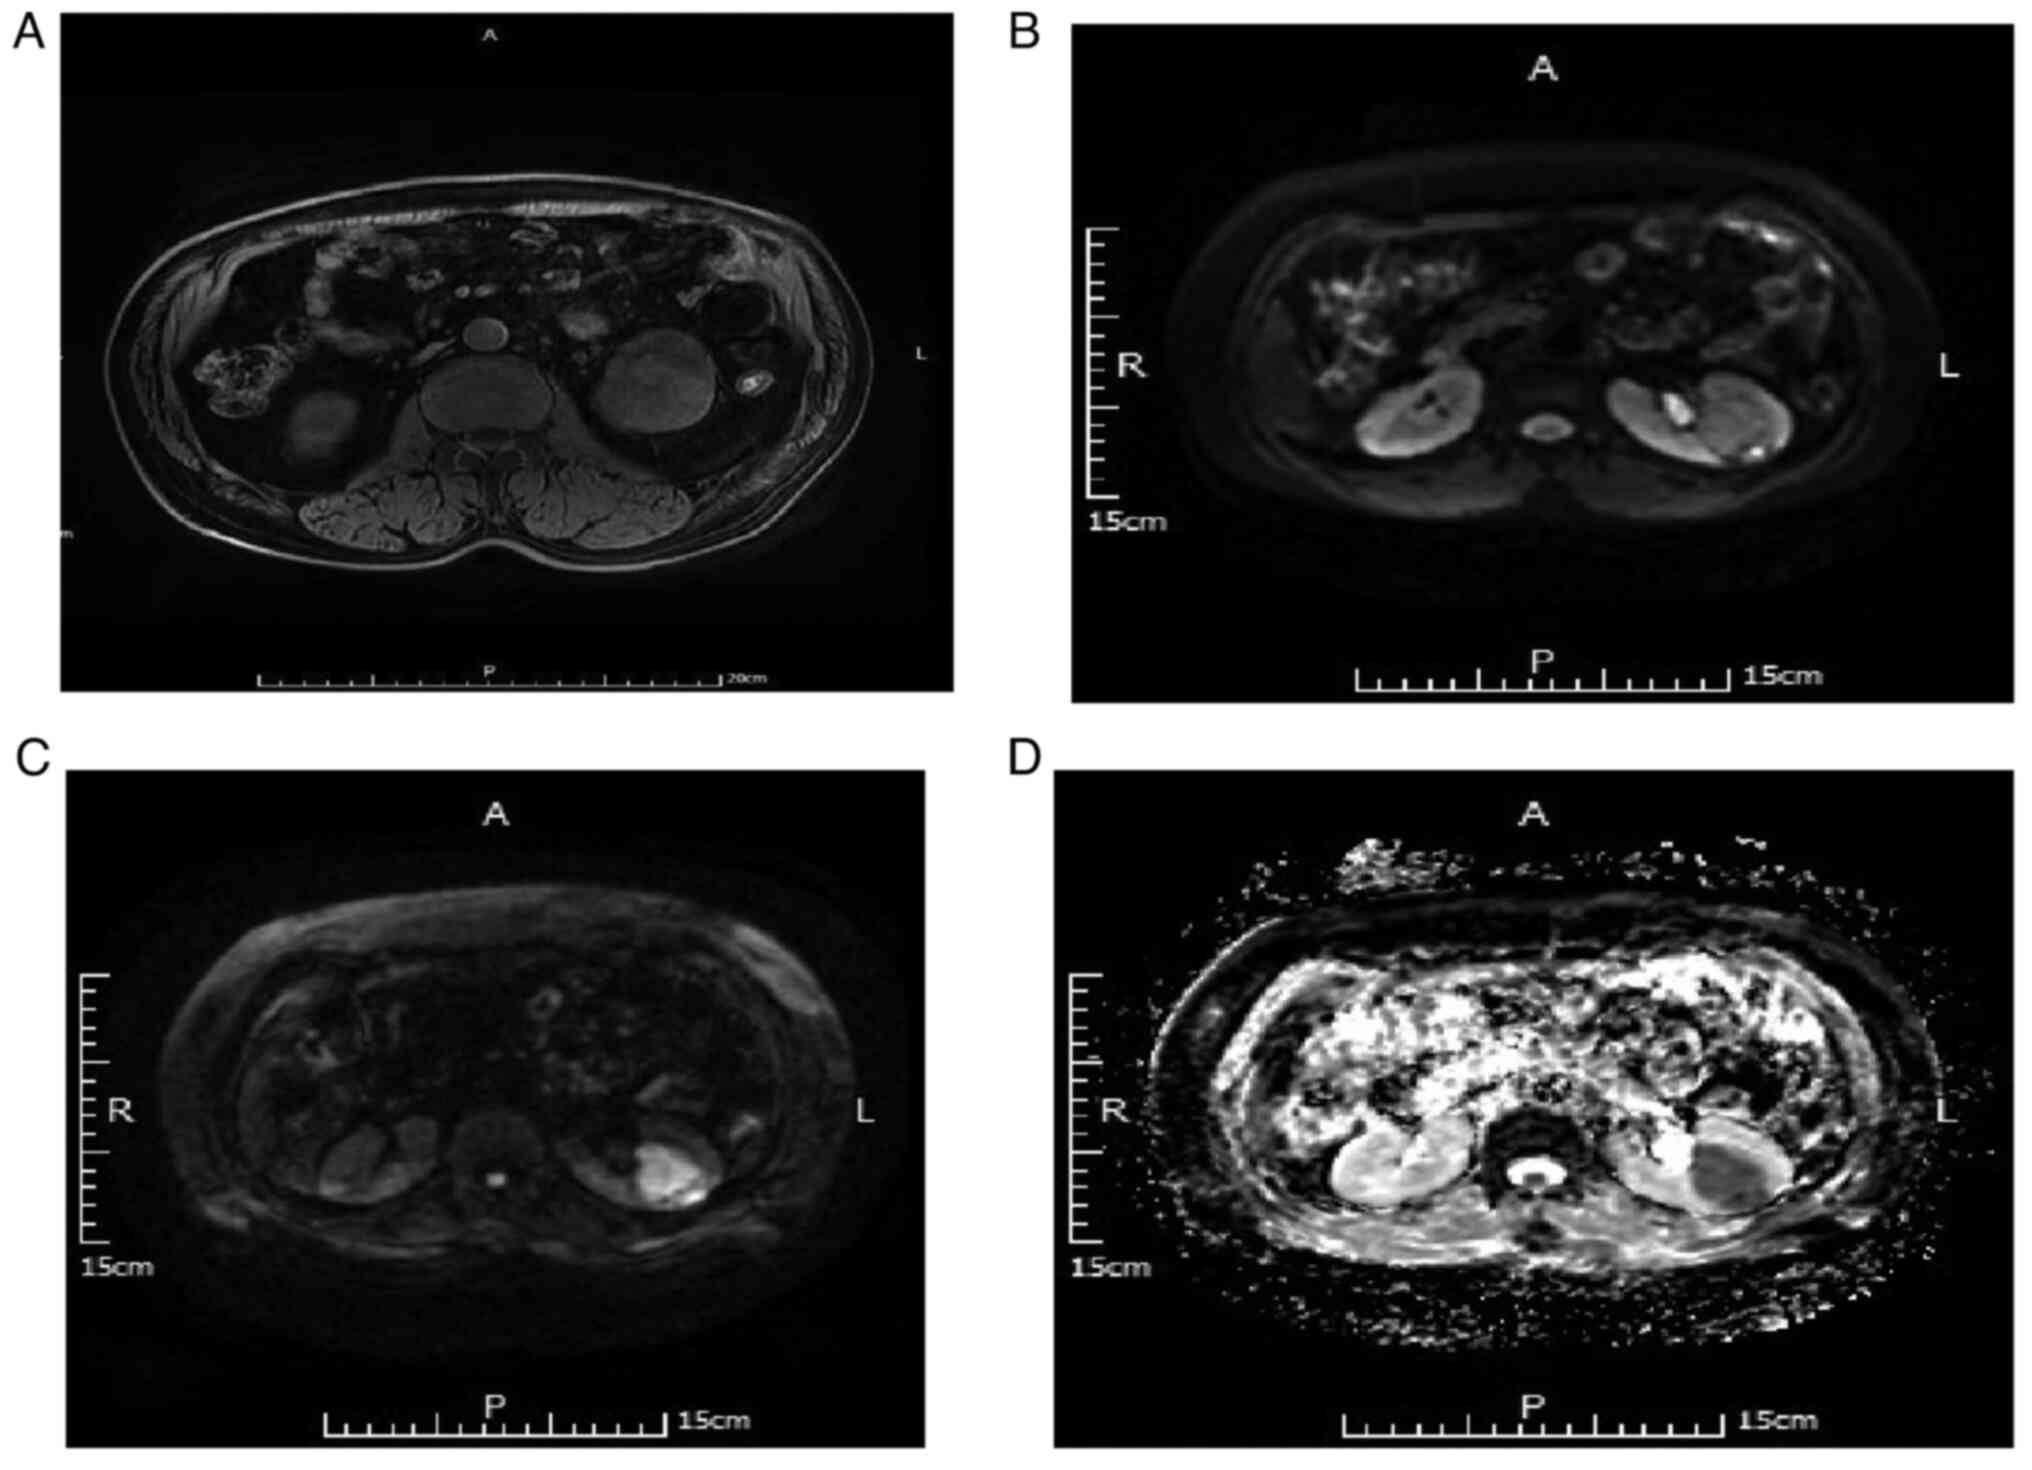

Imaging characteristics of DWI and ADC in the diagnosis of non-ccRCC

Of the 32 non-ccRCC cases, there were 21 cases of chromophobe cell carcinoma. For DWI B-value=50 s/mm2, 17 of the 21 cases (80.95%) were judged as a slightly high and four cases (19.05%) as high signal. For DWI B-value=800 s/mm2, five of the 21 cases (23.81%) were judged as high and 16 cases (76.19%) as significantly high signal. Additionally, for ADC, 4 cases (19.05%) were judged as low and 17 cases (80.95%) as significantly low signal. Representative MRI scans are depicted in Fig. 2.

Figure 2.

MRI scans of a 56-year-old male with pathologically confirmed chromophobe cell carcinoma of the left kidney. (A) T1WI, left renal tumor with low signal. (B) DWI B=50, left renal tumor with low signal. (C) DWI B=800, left renal tumor with obvious high signal. (D) Apparent diffusion coefficient with obviously low signal. DWI, diffusion-weighted imaging.